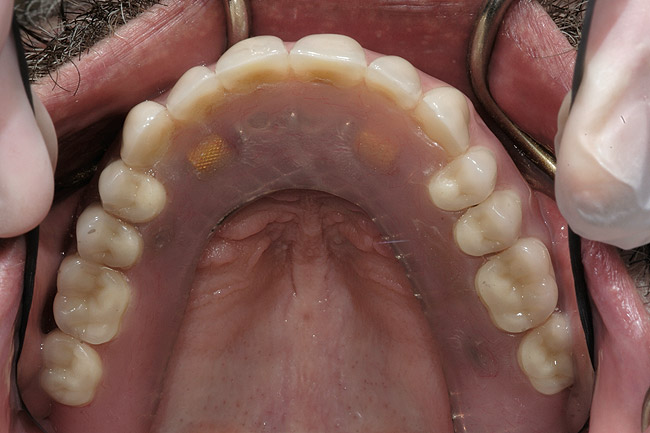

S-a conceput proteza provizorie imediată (fig. 6). Suprafaţa vestibulară a incisivului 2.1. era în poziţia orizontală dorită şi după scurtarea sa cu 3mm se afla şi în poziţia verticală dorită. Dintele 2.1. modificat a devenit apoi dintele „reper”, stabilind poziţia muchiei incizale. Laboratorului dentar i s-au oferit instrucţiuni pentru a înălţa dinţii superiori restanţi, menţinându-i la nivel cu poziţia scurtată a dintelui reper, cu întregirea planului ocluzal. Dinţii frontali inferiori au fost scurtaţi cu 2mm pe modelul diagnostic, stabilind poziţia muchiei incizale inferioare, iar laboratorul a fost instruit să închidă dimensiunea verticală de ocluzie cât era necesar pentru redobândirea contactului anterior dorit cu arcada superioară.

Proteza provizorie s-a apropiat extrem de mult de atingerea obiectivelor de ridicare a planului ocluzal pentru estetică şi repoziţionarea palatinală a incisivilor superiori (fig. 7). Încercarea de a eleva planul ocluzal a condus din punct de vedere estetic la situaţia în care planul ocluzal al protezei provizorii era superior faţă de acrilatul care acoperea tuberozitatea maxilară (fig. 8). În cursul perioadei de integrare, proteza provizorie a fost menţinută pe implanturile în curs de vindecare.